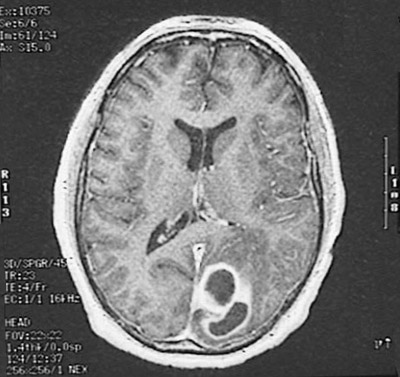

The MRI scan shown here in axial view demonstrates a couple of cerebral abscesses with enhancement at their periphery in the left occipital lobe.